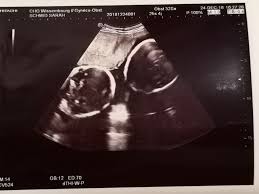

Es Sind Zwillinge Schmids Rasselbande Abenteuer Einer Grossfamilie